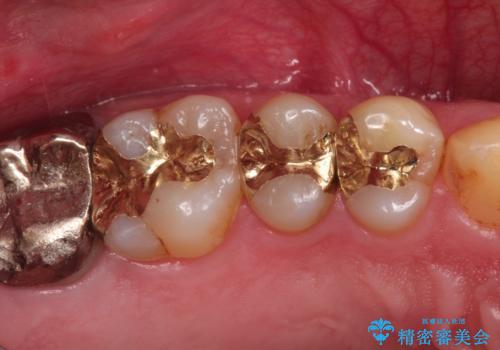

精密なむし歯の治療 ゴールドインレー

- 定期健診にてむし歯を認めたためゴールドインレーにて治療を行いました。

ゴールドインレーは適合が良く、割れることもないため、長期的に安定した治療法となります。